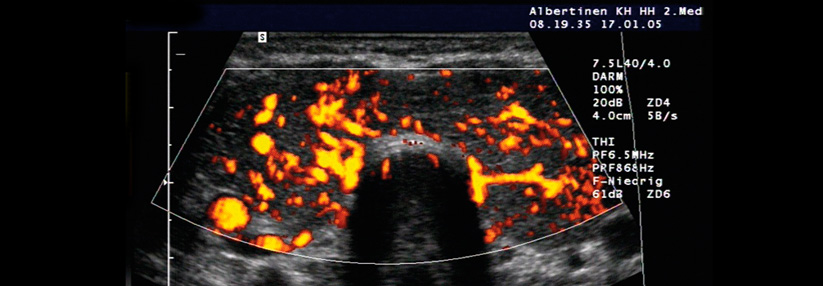

Im Zuge des Anstiegs bildgebender Untersuchungen werden auch immer häufiger Schilddrüseninzidentalome entdeckt. Dennoch erfordert nicht jeder Knoten gleich eine diagnostische Punktion. Fakt ist: Subklinische Schilddrüsenknoten findet man bei etwa jeder zweiten Frau im Alter von über 60 Jahren. Aber nur 5–10 % sind Karzinome. Punktieren sollte man nur Veränderungen, bei denen Ultraschallaufnahmen für einen Malignitätsverdacht sprechen, schreiben Dr. Natalie Rouiller vom Centre Hospitalier Universitaire Vaudois, Lausanne, und Kollegen.